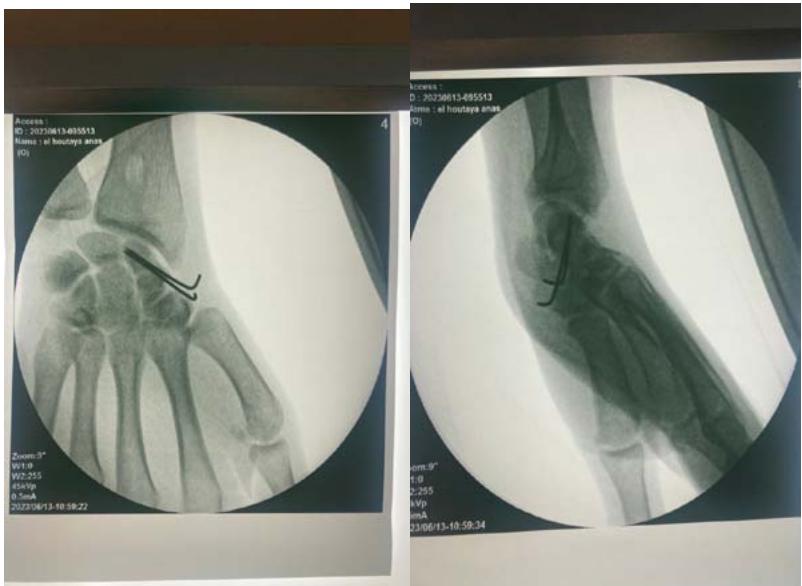

The patient underwent surgery via an anterior approach. Careful curettage of the cavity was performed after distraction of the fracture site. The bone defect was filled with autologous cancellous graft harvested from the lower metaphysis of the ipsilateral radius. Fracture stabilization was achieved with 2 pins (figure 3). The histopathological examination of the curettage specimen showed that the cyst wall was lined with flattened fibroblastic cells resembling synovial cells, without true epithelial appearance. There was no mucoid degeneration or myxoid transformation.

Figure 3: Postoperative radiograph after curettage, grafting, and stabilization with two pins.